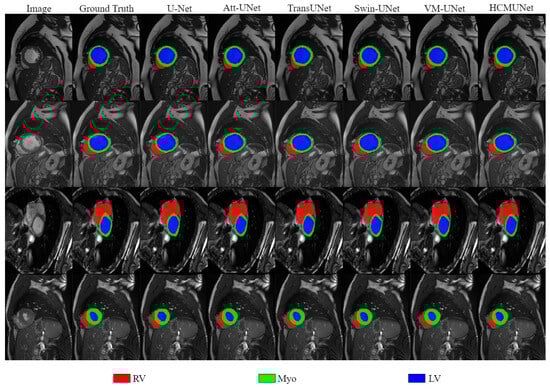

| Model | DSC | RV | MYO | LV |

|---|---|---|---|---|

| U-Net [2] | 87.84 ± 1.38 | 86.51 ± 1.32 | 84.66 ± 5.65 | 92.36 ± 3.92 |

| Att-UNet [19] | 88.04 ± 2.02 | 86.70 ± 2.33 | 84.59 ± 8.96 | 92.83 ± 1.57 |

| TransUNet [43] | 89.45 ± 1.13 | 87.85 ± 2.22 | 86.09 ± 2.23 | 94.39 ± 1.43 |

| nnUNet [22] | 90.14 ± 1.83 | 88.58 ± 1.44 | 89.72 ± 1.18 | 92.13 ± 2.24 |

| Swin-UNet [26] | 90.20 ± 0.78 | 87.44 ± 2.46 | 88.20 ± 3.40 | 94.97 ± 1.26 |

| LeViT-UNet [46] | 90.42 ± 1.15 | 88.85 ± 1.52 | 88.29 ± 2.04 | 94.12 ± 1.88 |

| HiFormer [47] | 90.69 ± 0.85 | 90.06 ± 1.30 | 89.00 ± 1.29 | 93.00 ± 1.07 |

| VM-UNet [12] | 90.72 ± 0.77 | 90.61 ± 1.67 | 89.40 ± 1.88 | 92.14 ± 0.76 |

| EMCAD [48] | 91.30 ± 0.35 | 90.17 ± 1.88 | 89.16 ± 1.24 | 94.55 ± 1.59 |

| TransCASCADE [49] | 91.59 ± 0.21 | 90.12 ± 2.66 | 90.14 ± 0.68 | 94.51 ± 2.55 |

| HCMUNet (Ours) | 92.11 ± 0.26 | 91.50 ± 0.78 | 90.20 ± 0.56 | 94.61 ± 1.12 |